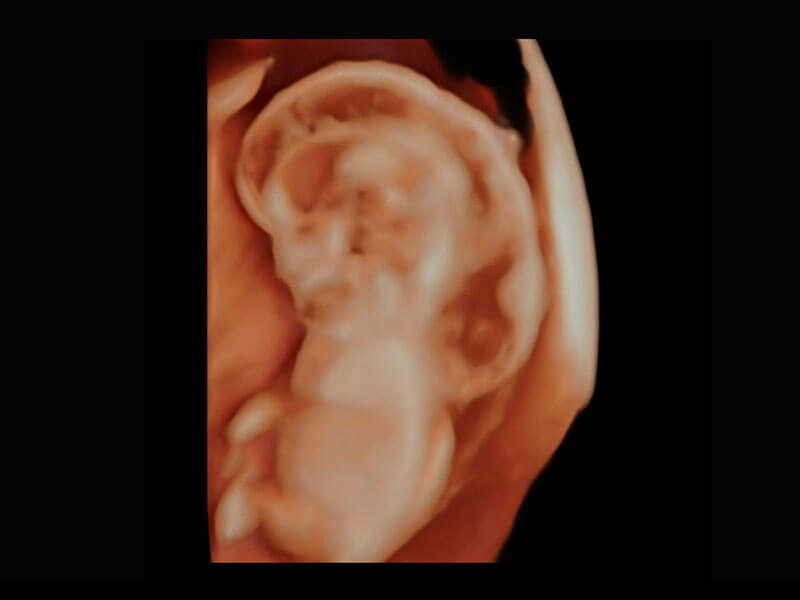

P60在胎儿早孕期超声筛查中为您带来优异的图像质量。

早孕-胎心

高分辨率容积成像-早孕胎儿

光影成像-孕囊